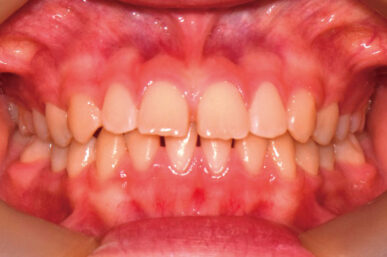

• Before

• After

出っ歯が気になるという事でしたが、下顎がさがっていました。治療開始が遅かったため生え代わりを待つ必要があり、治療期間が長くなりました。

下顎が正しい位置で噛むようになり、出っ歯に見えなくなりました。